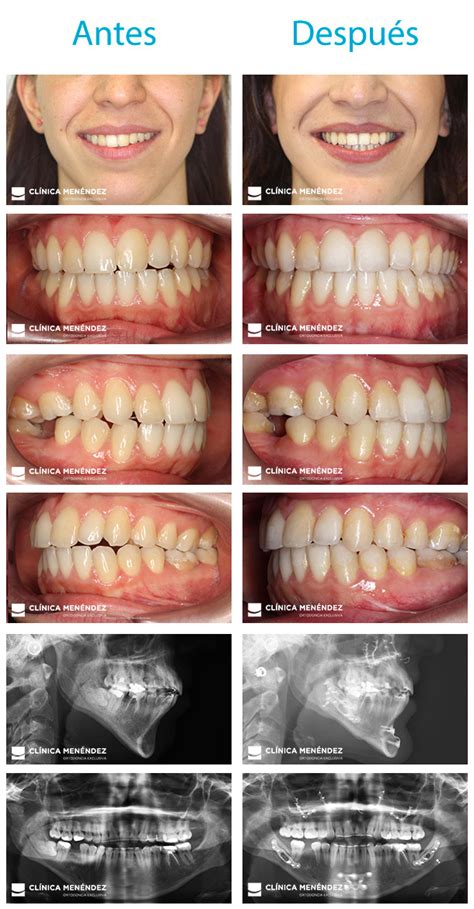

Casos de éxito: cirugía ortognática antes y después

Te presentamos las imágenes de antes y después de nuestro paciente.

Cirugía ortognática antes

Cirugía ortognática después